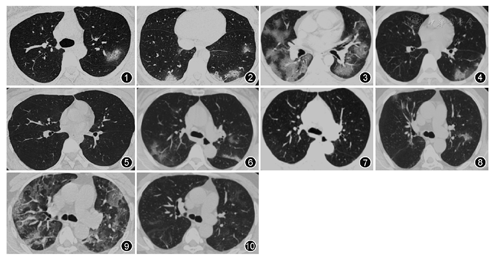

30例患者入院时均进行了胸部CT检查,所有患者发病初期均出现了肺部影像学改变,主要表现为多发小斑片影及间质改变,短期内病灶迅速增多,进展为双肺多发磨玻璃影及浸润影,恢复期部分患者可出现实变及纤维条索影。肺炎累及单侧者11例(36.67%),累及双肺者19例(63.33%),其中4例(13.33%)表现为典型的双肺弥漫性磨玻璃样改变,具体见图1,图2,图3。肺部病灶完全或基本吸收者19例(63.33%),部分吸收者9例(30%),无吸收甚至肺部阴影增多者2例(6.67%)。具体见图4,图5,图6,图7,图8,图9,图10。CT影像学随着疾病的进展呈现出发病期、进展期及恢复期的动态演变过程,发病至进展期平均(7.62±2.28)d,进展期至恢复期平均(16±7)d。